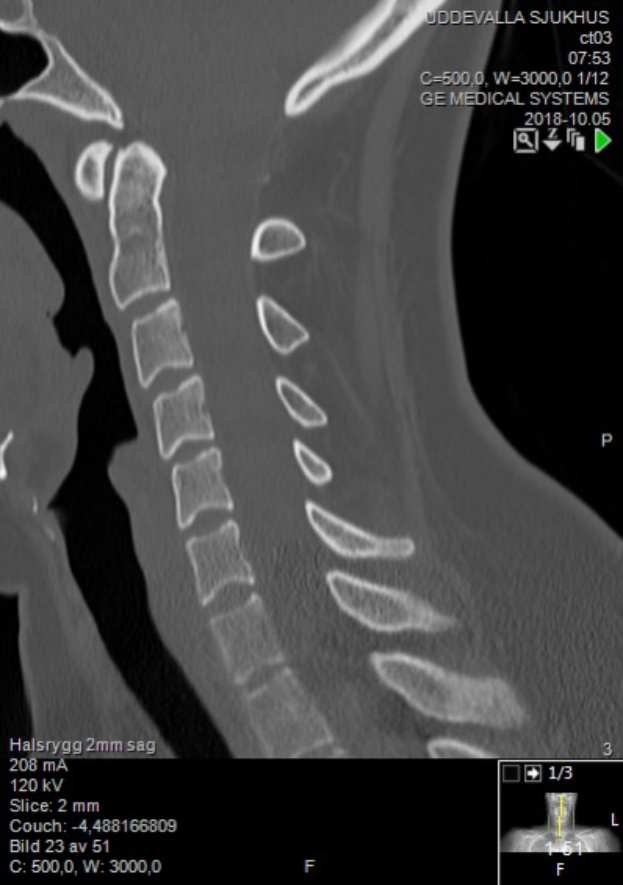

Ein Röntgenbild eines Mannes mit einem sichtbaren Bruch in der Mitte, das auf einem Computerbildschirm mit Text und Zahlen angezeigt wird.Evi Heuser